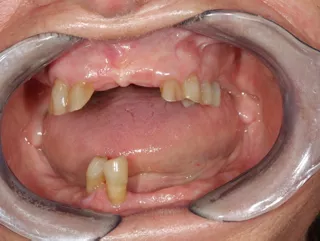

Initial situation

Clinical examination with x-ray showing a poor prospective for long-term prosthetic life of teeth on the lower jaw. In the upper jaw, teeth 13, 12, 22, 23, 24 and 25 were permanently preserved following preliminary treatment.

2. Display of teeth once pretreatment was completed. Treatment plan for the implant positions done using CBCT and intraoral scans at this stage.